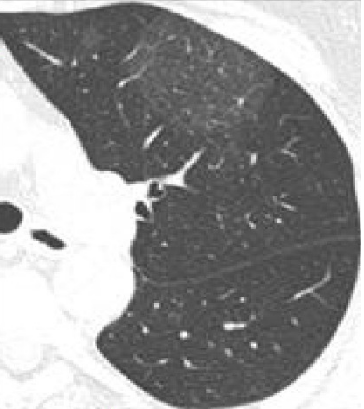

胸廊对称,左上肺磨玻璃病灶,形态不规则,边缘尚清,其规格16.6X11.4mm,其内密度欠均匀,局部胸膜粘连,

检查所见:双侧胸廓饱满,双肺血气管纹理增多,右肺上叶见一不规则磨玻璃密度结节,大小约2.4cm×1.8cm,